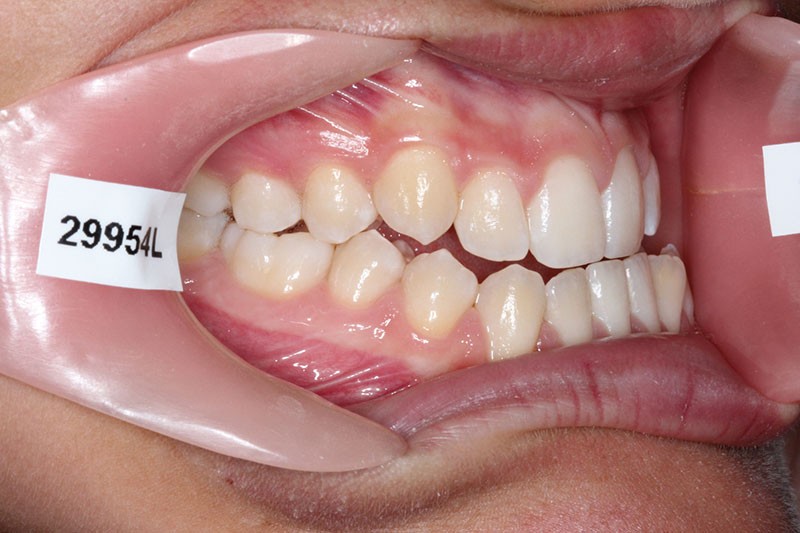

Nous sommes en présence d’une patiente en fin de croissance faciale, âgée de 16 ans. Elle présente une classe III dentaire et squelettique associée à une asymétrie faciale de type latérognathie mandibulaire avec déviation des points interincisifs et déviation du menton vers la gauche.

Pour des raisons personnelles, la patiente refuse un protocole orthodontico-chirurgical. Nous optons pour une réduction de la classe III par compensations dento-alvéolaires car la progénie n’est pas très importante et nous estimons que le résultat dentaire, squelettique et facial peut être cohérent. Un système « Motion Classe III Carriere » va être utilisé suivi d’un appareillage multibague « Carriere SLX ».